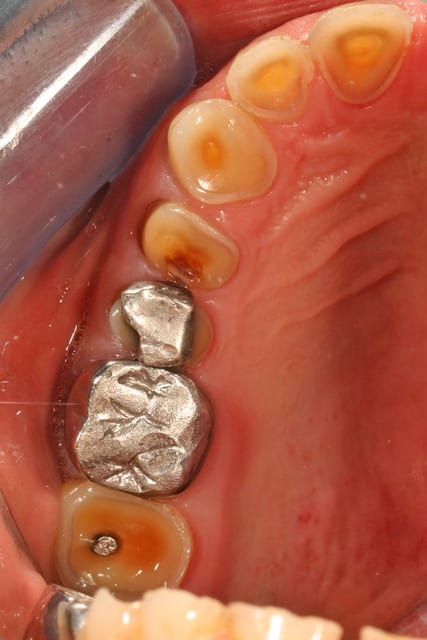

voilà un patient venu en urgence pour sa 36 descellée depuis plus d'un mois, que je n'ai pas pu resceller cause egression de la dent et couronne super fine que j'aurais trouée de partout en la retouchant

les modèles d'étude

on voit bien l'abrasion liée au bruxisme

l'érosion liée à l'acidité (une bière tous les soirs avant le repas, une pomme tous les soirs en dehors du repas)

l'usure des prémos liée a de mauvaises habitudes dans son métier (tournevis ou stylo au coin de la bouche)